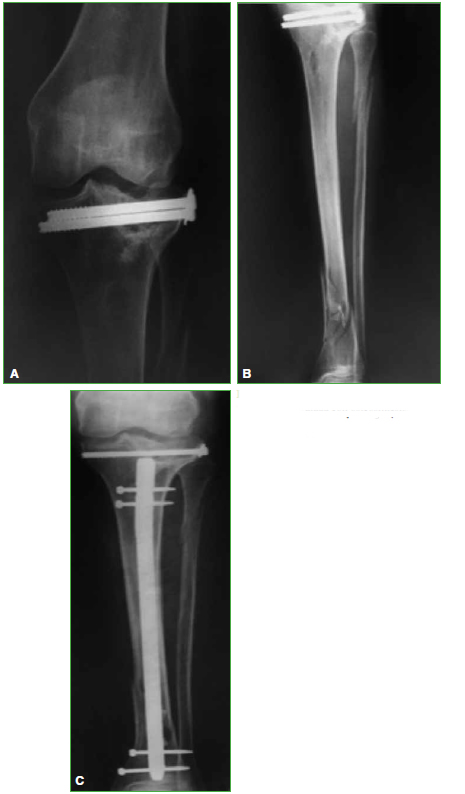

Materiales y Métodos: Estudio retrospectivo observacional, entre mayo de 1999 y enero de 2013. Se evaluaron 25 RTR en 24 pacientes (edad promedio 67.1 años) con secuela de fractura articular de rodilla y un seguimiento promedio de 6.1 años. Tres (12%) tenían cirugías anteriores al RTR. Ocho se resolvieron en dos tiempos. Se empleó un implante constreñido en 4 pacientes (16%). Se determinaron el KSS, el KSSf y el rango de movilidad preoperatorios y del último control. Se documentó la supervivencia del implante.

Resultados: El KSS se incrementó de 38,5 en el preoperatorio a 82,8 en promedio. El KSSf posoperatorio mejoró de 48 a 85. El rango de movilidad aumentó de un promedio de 7,5-76° a 1-102,4° en el posoperatorio. Cuatro casos fueron reoperados. La supervivencia de la prótesis fue del 92% a los 6.1 años.

Conclusiones: El RTR es adecuado para la gonartrosis postraumática en su estadio final, con buenos resultados a mediano plazo. Si se logran una adecuada alineación posoperatoria y un correcto posicionamiento de los componentes, los resultados son satisfactorios y se asemejan a los del RTR por gonartrosis idiopática.